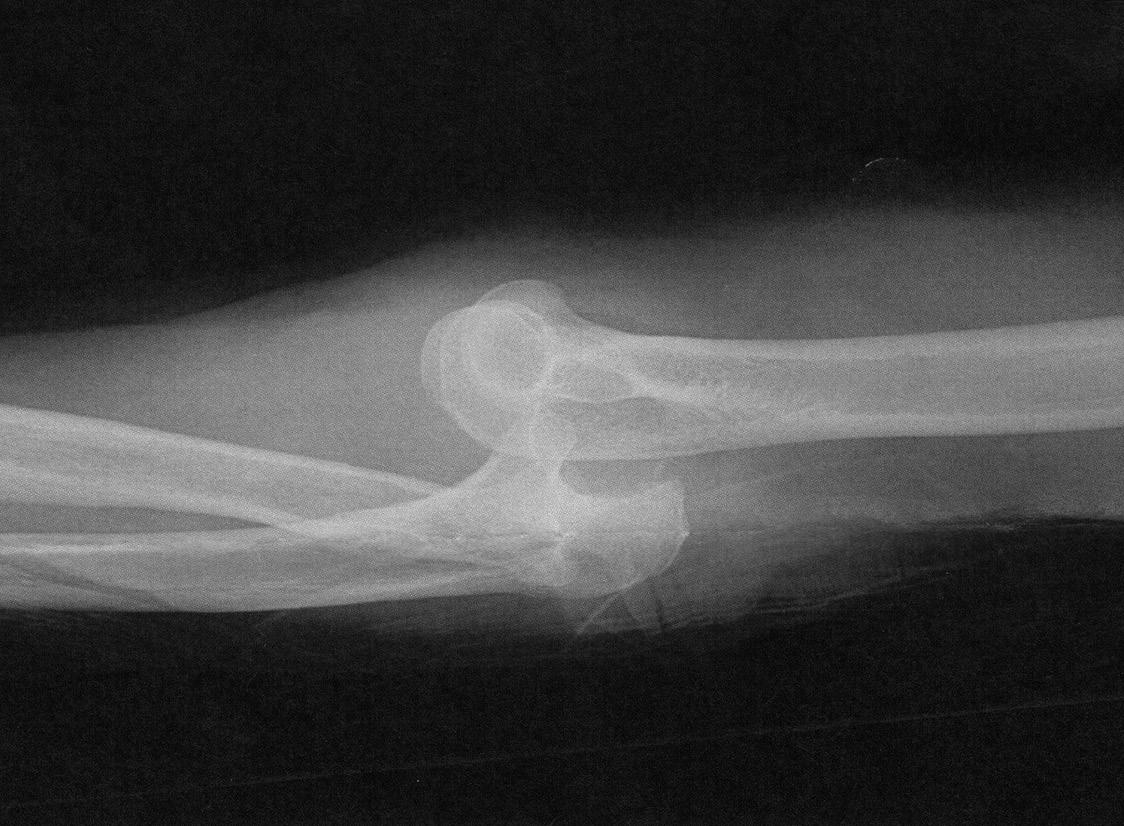

Life took a hard turn for Steve Rollins on December 2, 2022.

The longtime Sisters mechanic took a bad fall at his home shop that left him with spinal cord injuries and facing a long road to recovery.

“He slipped on ice,” his son Jeremy Rollins told The Nugget. “He said the last thing he remembered was the ground coming up at him.”

What happened, though, was worse than hitting the ground. Rollins fell face-first into the hydraulic arm of a floor hoist used for lifting car engines. The steel cut into

Rollin’s forehead, leaving a nasty gash. But the most serious injury was to his neck. The impact whipped his head back and caused his cervical vertebrae to compress his spinal cord.

He lay on the ground for an estimated hour before his dog found him and alerted another person living on the property, who summoned help.

The fall left Rollins in a state of “incomplete quadriplegia,” meaning that he has some movement, but not with complete control, of his arms and legs.

A surgeon operated to relieve pressure on his spinal

See RECOVERY on page 4

cord, and he spent weeks in rehab at St. Charles Hospital.

“Dad’s very lucky to be alive, is what it comes down to” Jeremy said. “If he wasn’t the tough, stubborn ol’ boy that he is, I don’t know if he’d have lived through it.”

Rollins is, in fact, doing well, though he has his ups and downs. His left arm functions well enough for him to feed himself or drink from a cup with a straw, or operate a motor wheelchair. And he’s gained more motion with his right arm in recent days. A home health team visits every day and he works on rehabbing his injuries — which is complicated by a raft of previous injuries and arthritis that had him pretty banged up even before his catastrophic fall.

While he was pleased with where he was last Sunday, Rollins and his family know there is a long haul in front of him. His son Jeremy and daughter-in-law Tonya told The Nugget that his surgeon said that a prognosis is difficult to nail down with this type of spinal injury: Some bounce back amazingly quickly; some never regain function; some take a year or two to regain some or most of their function.